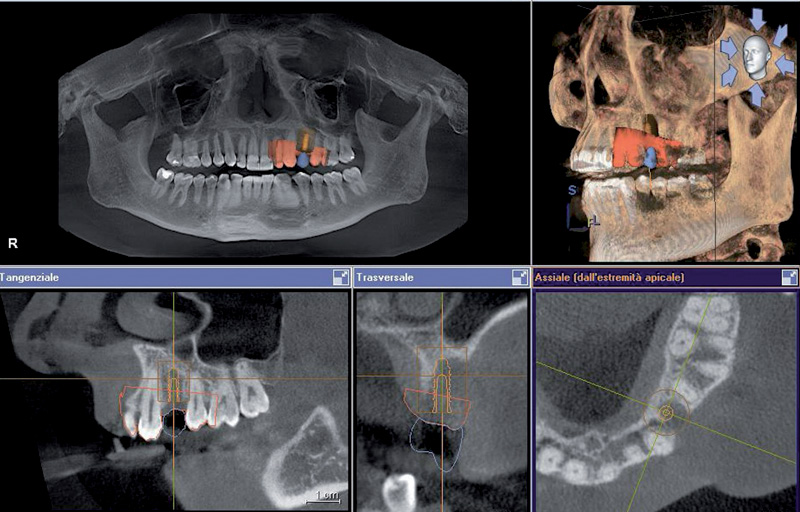

Si esegue una ceratura virtuale sul modello tridimensionale digitale ottenuto dalla scansione ottica intraorale eseguita con sistema Cerec (Sirona). Il paziente viene sottoposto, nella medesima seduta, alla scansione radiologica tramite CT Cone Beam (Galileos Sirona). L’integrazione o “matching” del modello 3D ottico con il modello 3D radiologico fornisce un unico modello digitale tridimensionale di assoluta precisione. Si sceglie, dalla libreria del software, il tipo di impianto e il suo posizionamento, visualizzando immagine radiologica, tessuti molli e corona protesica (Fig. 1).8j8

- Fig. 1

Dopo 4 settimane dall’estrazione si è proceduto in un unico appuntamento ad eseguire la scansione intraorale (Fig. 4) e, su questa, la ceratura virtuale dell’area edentula (Figg. 5, 6), la Rx endorale (Fig. 7) e l’esame TC Cone Beam (Fig. 8); infine si è effettuato il matching dei due dati digitali (Fig. 1) e si è scelto tipo e posizione dell’impianto. Come si può notare dalle immagini, a sole 4 settimane dall’estrazione il sito presentava insufficiente disponibilità, mostrando soprattutto la completa assenza della corticale vestibolare. La pianificazione del caso prevedeva, nonostante la presenza della dima chirurgica per il posizionamento dell’impianto, l’apertura di un lembo chirurgico per rigenerare contestualmente la componente ossea vestibolare.

- Fig. 8

Viene scelto, dalla libreria del software, l’impianto: la scelta ricade su un impianto Leone 3,3 x 10 mm. Questo viene posizionato in funzione della protesi progettata. La procedura è stata effettuata davanti al paziente, che partecipava attivamente e ne comprendeva il significato.